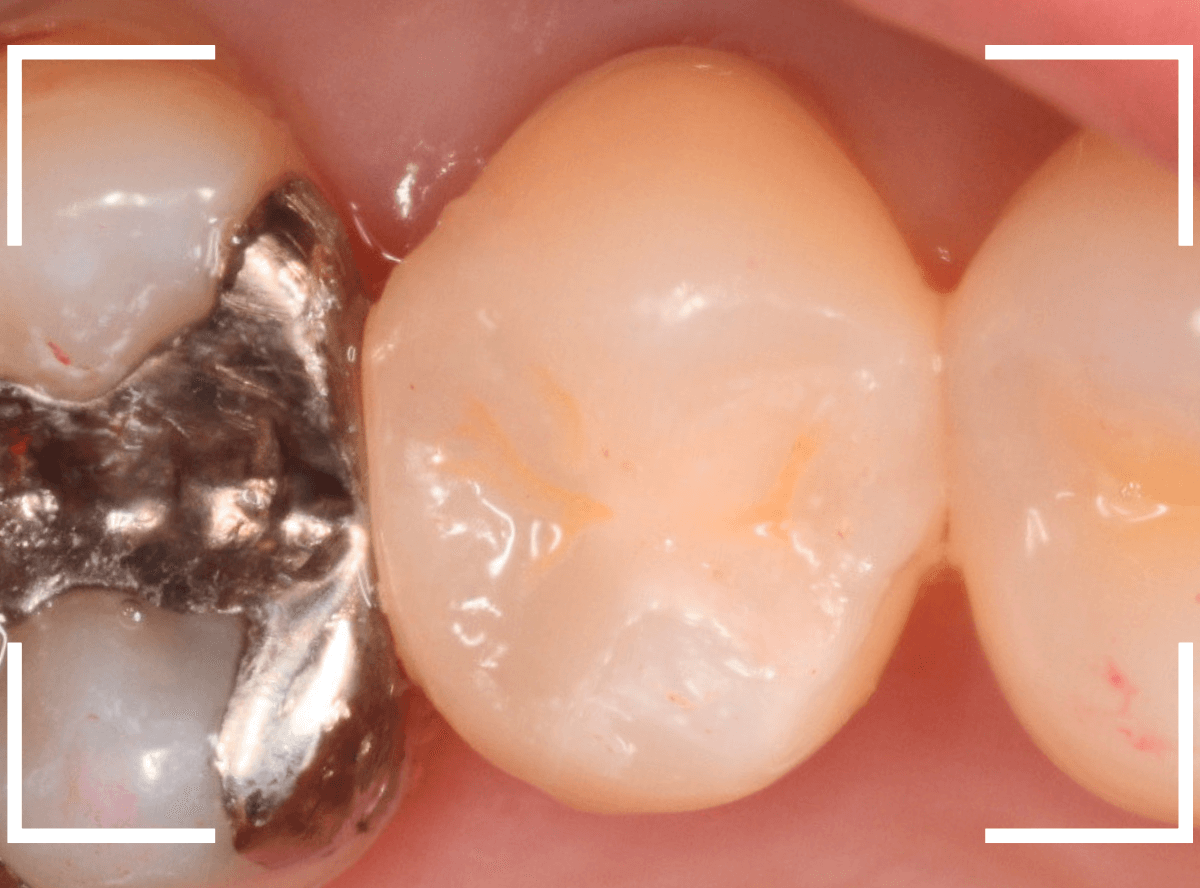

治療を始めて、虫歯の部分をう蝕検知液で染め出したところです。

真っ赤ですね。

慎重に虫歯を除去しますが、まだ虫歯が残っています。

虫歯を除去しました。

なんとか神経ぎりぎりのところで踏みとどまりまし

た(^^;)